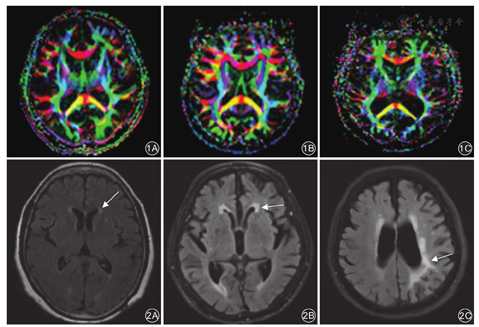

采用德国Siemens MAGNETOM Verio 3.0 T MR扫描仪。所有患者行自旋回波序列头部T1WI、T2WI及FLAIR横断位和T1WI矢状位扫描。T1WI参数:TR 450 ms、TE 15 ms,T2WI参数:TR 4 000 ms、TE 120 ms。根据需要再行各相冠状位扫描,层厚3~6 mm,层间距0.3~0.6 mm。DTI检查的扫描参数:TR 6 000 ms,TE 90 ms,层厚3 mm,层间隔0~1 mm,视野240 mm×240 mm,矩阵128×128,平均激励次数3,b值为0、1 000 ms/mm2,扩散特征是沿着20个非共线方向测量。数据采集完成后,运用荷兰Philips Extended MR工作站R2.6.3.4软件进行分析,重建出各向异性分数(fractional anisotropy, FA)图、表观扩散系数(apparent diffusion coefficont, ADC)图。在FA轴位图不同层面上选择感兴趣区,测量FA值、ADC值。见图1。

WML的诊断及分级:WML通过颅脑MR T2WI和FLAIR像进行诊断,表现为斑点状或片状病变,见图2;按照病变部位分为脑室旁白质WML和皮质下WML。WML的严重程度判定参照修订后的Fazekas VAS[12],共分为4个等级:(1)无WML为0分;(2)轻度为1分,单个病灶直径<10 mm,所有病灶直径总和<20 mm;(3)中度为2分,存在融合的病变,但病变中无桥状连接,单个病灶直径为10~20 mm,所有病灶直径总和≥20 mm;(4)重度为3分,单个或融合性病损≥20 mm。

对照组和AD痴呆组分别检测了23例和48例不同区域脑组织的FA值和ADC值。DTI分析显示:两组间额叶和半卵圆区的FA值、ADC值以及顶叶的FA值比较,差异均有统计学意义(P值均<0.05);两组间颞叶和枕叶的FA值、ADC值以及顶叶的ADC值比较,差异均无统计学意义(P值均>0.05)。见表4。